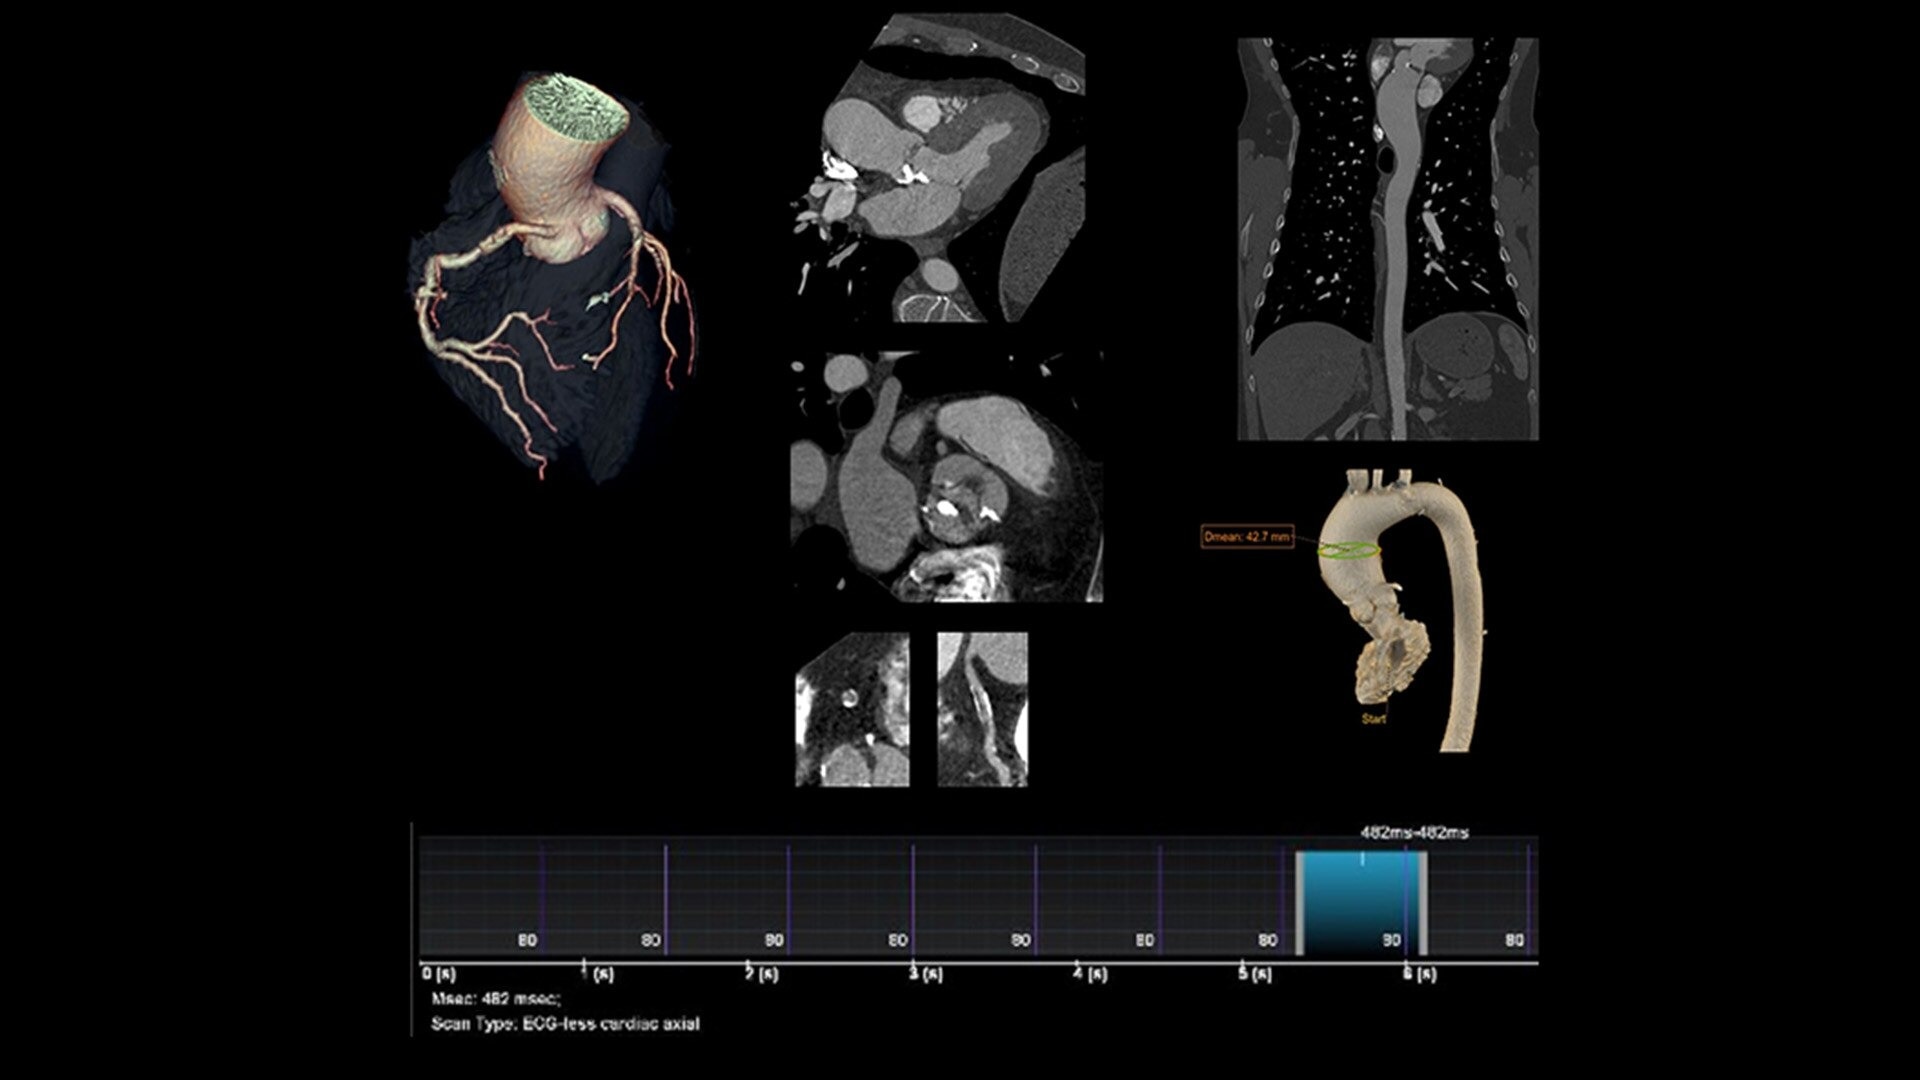

The ECG-less CT (a cardiac CT scan without an ECG trace) is an industry-first

Increases Cardiac CT access

Address cardiac exams where patient access and speed need to be prioritized

Simplified workflow

Useful in exams where excluding ECG traces would streamline patient preparation